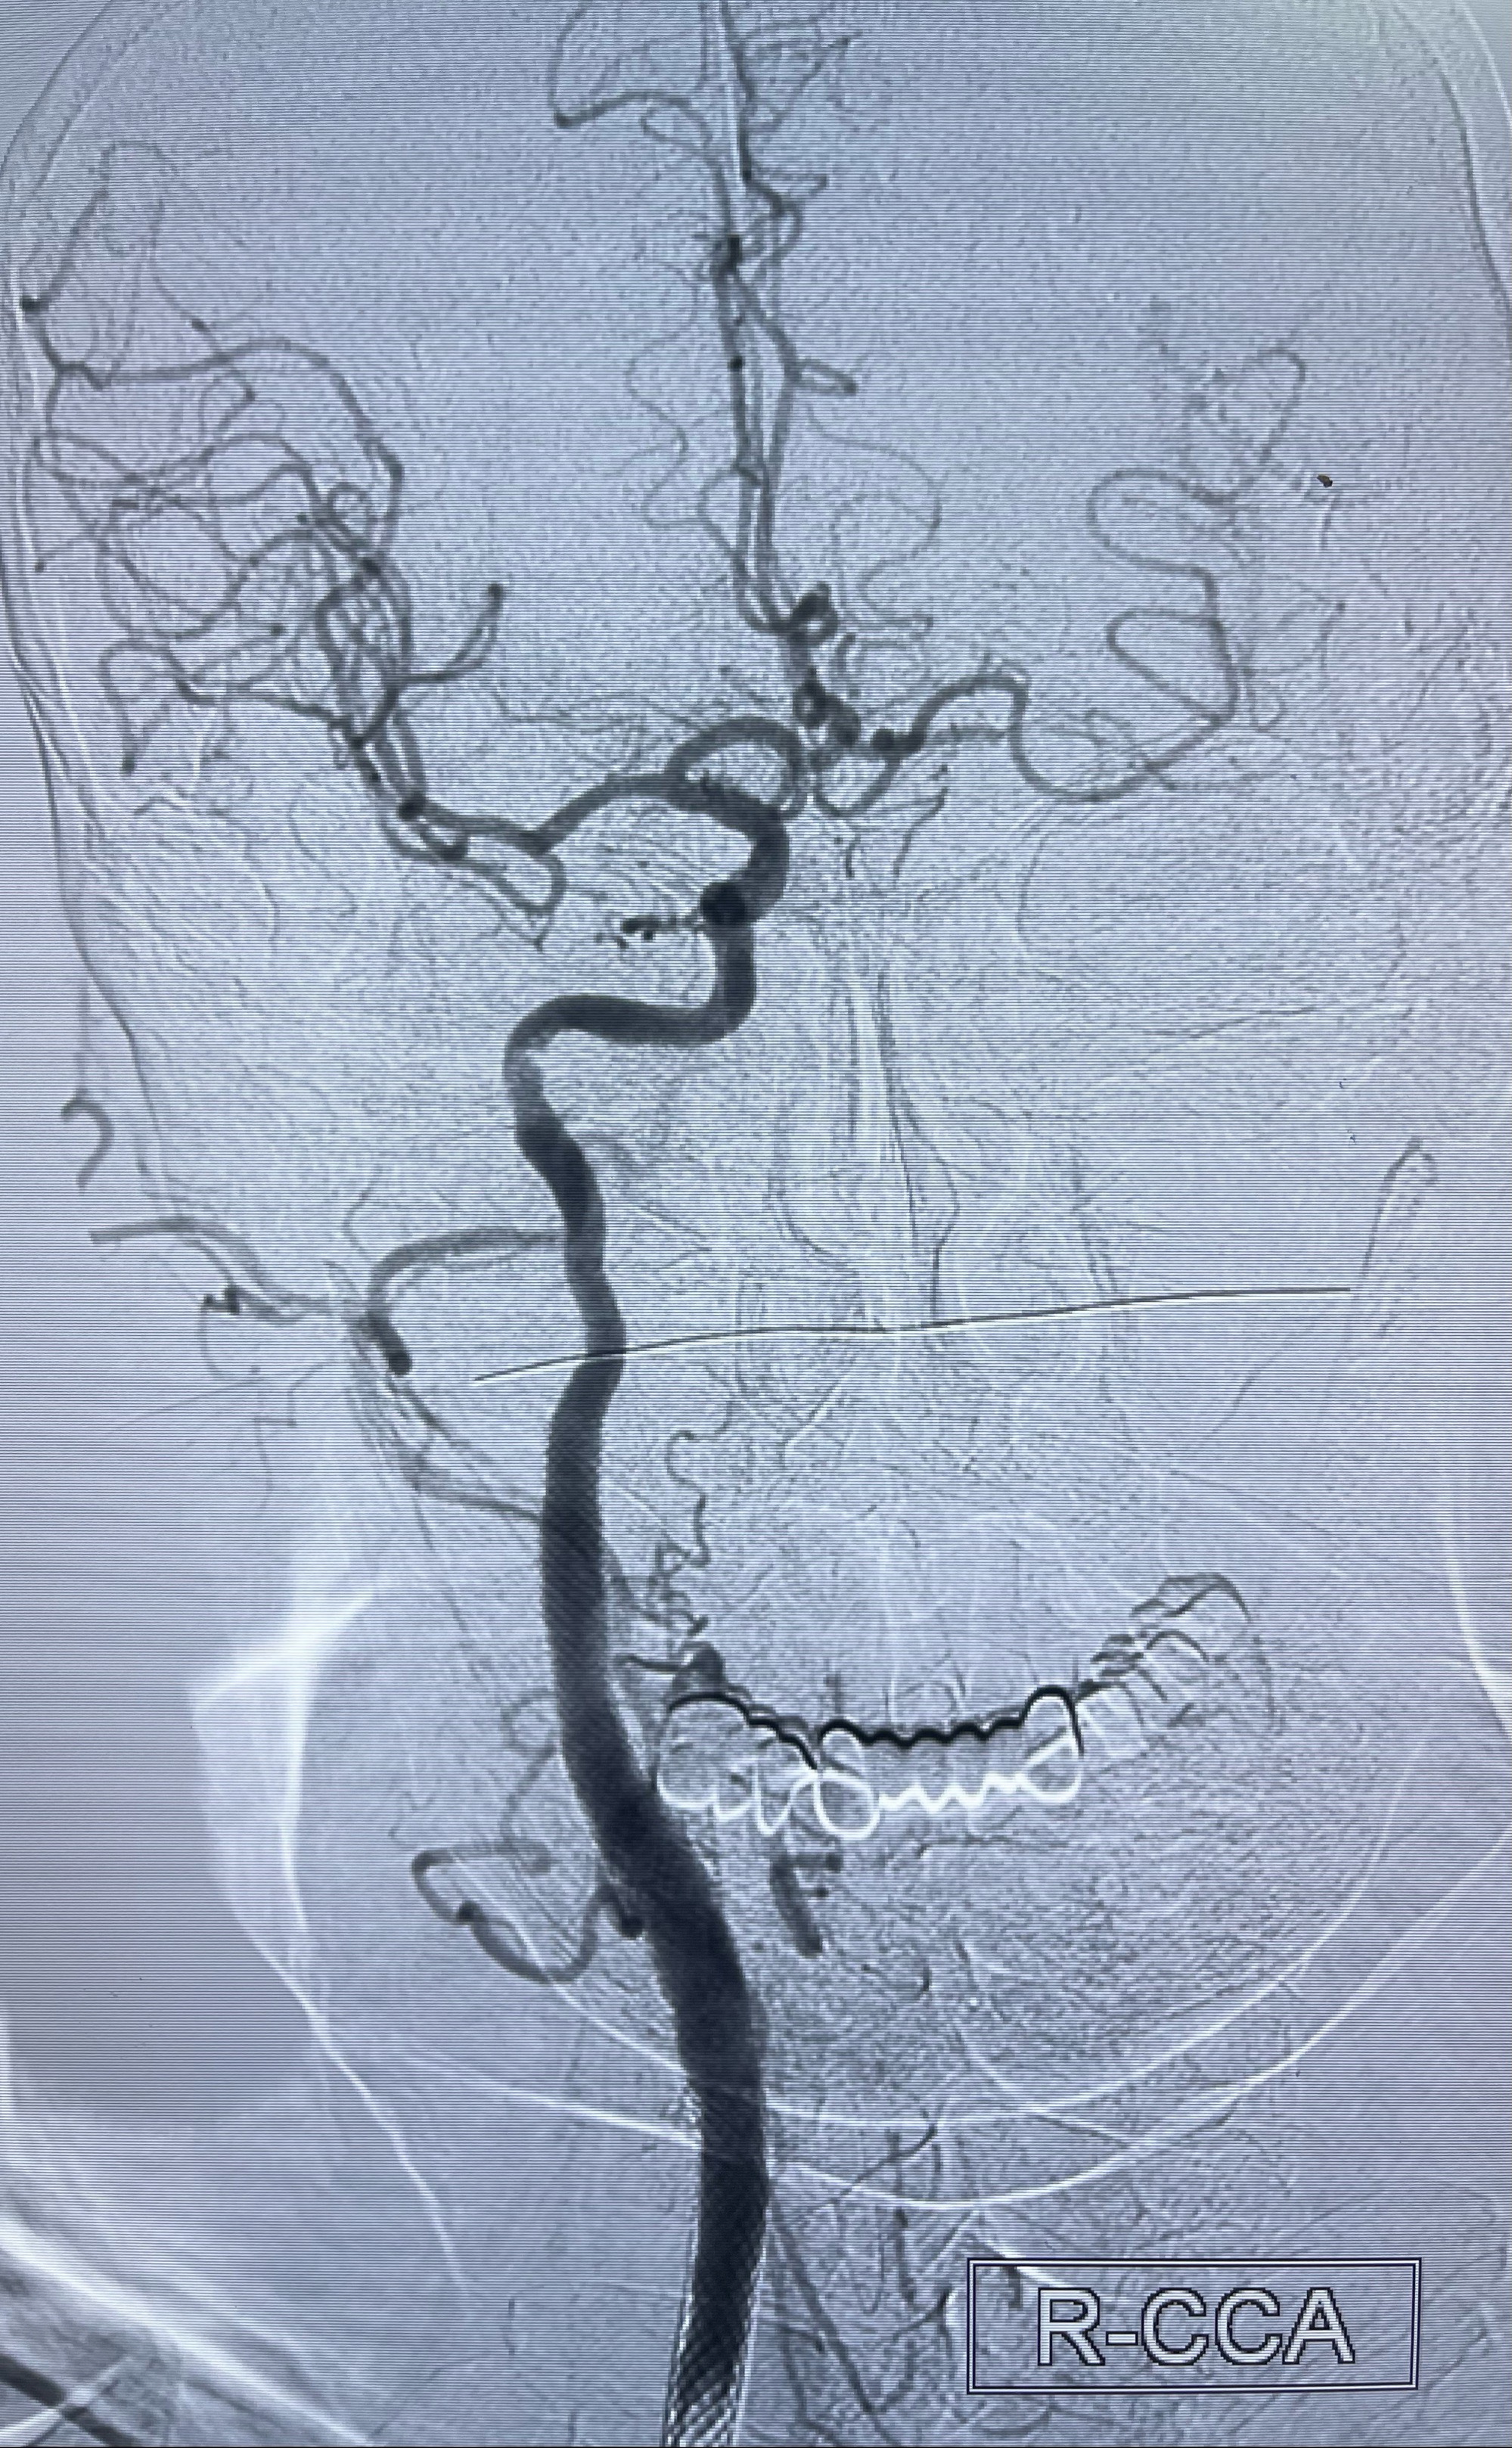

2023-07-10DSA:右侧颈内动脉岩骨段夹层伴中偏重度狭窄改变,左侧颈总动脉闭塞、右侧颈外动脉由右侧肋颈干甲颈干吻合代偿

箭头所示为颈内动脉岩骨段重度狭窄,结合MRI,考虑为肿瘤侵犯右侧颈内动脉

箭头以近至支架段管腔不规则狭窄

即刻造影显示狭窄扩张佳

即刻造影显示支架贴壁佳

支架完全打开,近心端位于原颈动脉支架远心端内